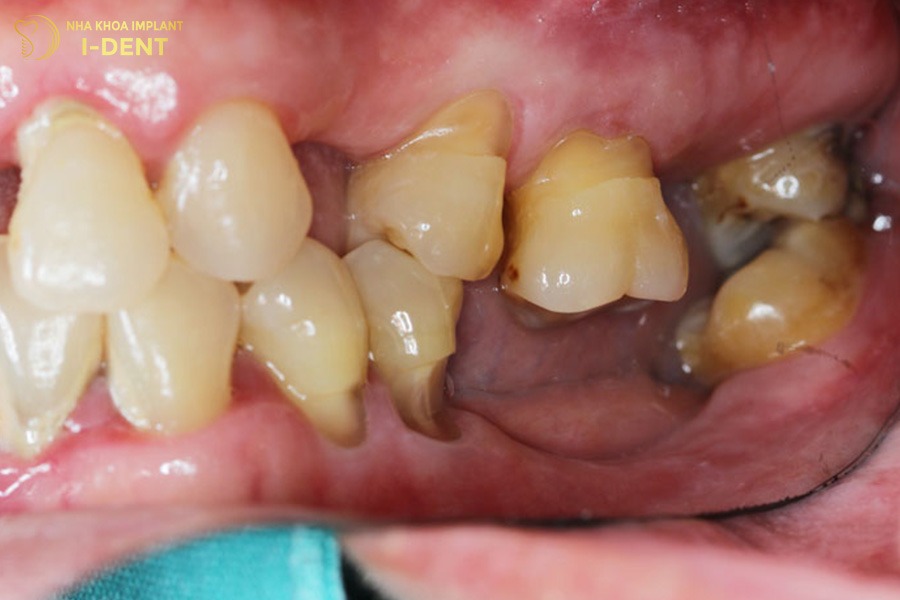

- Sai lệch khớp cắn: Sau khi mất răng, các răng kế cận có xu hướng nghiêng và đổ dồn về khoảng trống mất răng, trong khi răng đối diện lại mọc trồi lên hoặc xuống, làm cho khớp cắn bị lệch. Đồng thời, lực nhai phân bố không đều và các răng còn lại phải hoạt động nhiều hơn làm răng dần yếu đi, dễ lung lay hoặc gãy rụng.

2.6. Răng lung lay, yếu và đau khi nhai

Răng trở nên lung lay hoặc yếu đi là một trong những dấu hiệu rõ ràng nhất của tiêu xương răng. Khi xương ổ răng bị tiêu, răng không còn điểm tựa vững chắc nên bị lung lay gây ra cảm giác đau âm ỉ và ê buốt khi ăn nhai.

Nguyên nhân chủ yếu thường xuất phát từ vệ sinh răng miệng kém khiến mảng bám và vi khuẩn tích tụ quanh chân răng gây viêm nha chu. Quá trình viêm này diễn ra âm thầm trong thời gian dài, phá hủy dần mô nâng đỡ và xương quanh răng. Khi mô xương không còn đủ để giữ răng thì bệnh nhân có thể cảm thấy đau, khó nhai hoặc mất răng hoàn toàn nếu không được điều trị kịp thời.

Răng lung lay, yếu và đau khi nhai.